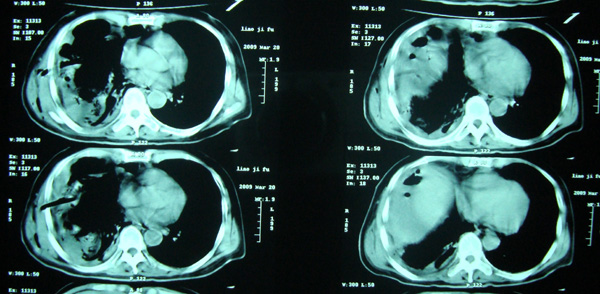

经治疗至17日胸闷痛摄片如9号图,20日复查如7,8号片.

结论:右侧大量胸腔积液,可疑膈下脓肿.

20日院外ct检查,片示于后.

有瘘道进入右侧胸壁

从侧位平片看,有气体影,结合断层考虑膈下脓肿

膈下可见气液平面,结合临床应该考虑膈下脓肿并同侧胸腔积液(脓)

右侧膈肌抬高明显,胸腔内无明显积液,表现为胸膜反应,肝脏周围大量积液,并见多个液气平面。右下肺不均匀密度增高影。结合临床考虑右侧膈下脓肿并腹腔内积液、右下肺并发感染及胸膜反应,节段性肺不张不除外。

右肺下叶见大片状病灶,密度不均,其内见透光区。沿右侧胸壁见多发含气腔,其间可见间隔,其内部分可见液平。膈肌下未见异常(纵隔窗窗位太低)。应该是典型的化脓性肺炎合并脓胸。

右隔下积脓并右侧肺脓肿;右侧液气胸